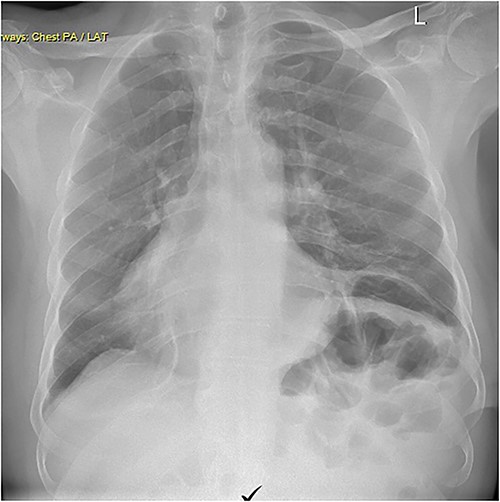

A 79-year-old male was referred by his general practitioner for consideration for repair of diaphragm eventration. The elevated left hemidiaphragm was noted on chest X-ray approximately a decade before. Referral was prompted by an episode of postprandial shortness of breath and a long-standing inability to belch. Medical history is significant for hypertension and tachyarrhythmia controlled on Flecainide. Clinical examination was remarkable for the presence of bowel sounds in the left chest at the level of the nipple, and apex beat on the right. Chest X-ray showed a markedly elevated left hemidiaphragm with dextrocardia (Fig. 1). Pulmonary function tests (PFT) showed small airway defect with normal lung volumes and diffusion capacity. Chest computed tomography showed no pathology other than the eventration.